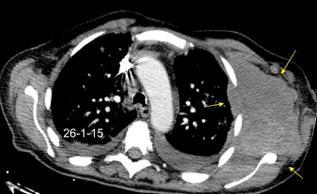

Masa axilar izquierda y derrame pleural derecho. Implantes pleurales, paraespinales . Ganglios en mamaria interna. Linfoma B difuso

Jaffe ES. Diagnosis and Classification of Lymphoma: Impact of Technical Advances.

2005. Masa pulmonar.

Linfoma NH de cél. B. Invasión Transtorácica.

Afectación axilar